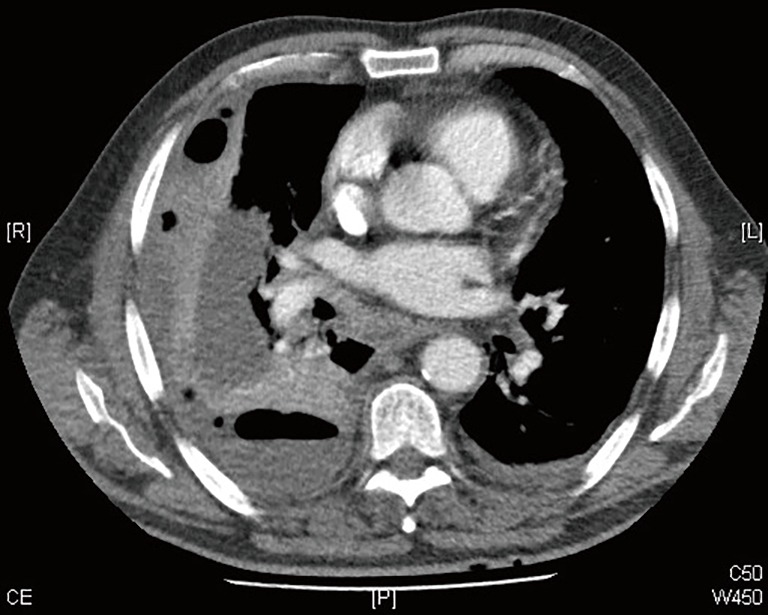

Figure 2.

Computer tomography of the same patient as in Figure 1.